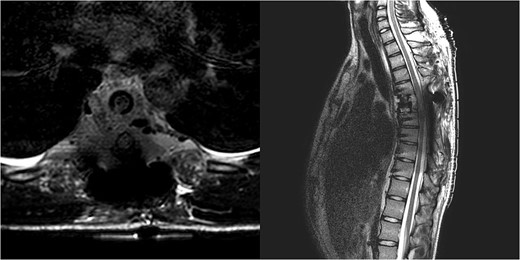

Three and a half years prior to admission to our institution, the patient underwent emergent Th6 vertebroplasty with laminectomy for a radiologically characteristic and histologically confirmed Th6 AVH causing acute thoracic myelopathy with a week-long paresis of the right foot dorsiflexion, performed by another surgeon. A progressive kyphotic deformity of the Th6 vertebrae was observed on radiographic follow-ups, whereby the hypoesthesia on the right anterior thigh persisted (ASIA score D, VAS pain score 7). Follow-up MRI and CT imaging revealed recurrent AVH of the Th6 vertebrae expanding into the spinal canal, leading to newly recognized worsening of myelopathy (Fig. 1). Additionally, a concomitant haemangioma was observed in the right transverse and articular process of Th8 (Fig. 2).

Follow-up CT imaging revealed recurrent AVH of the Th6 vertebrae, MRI scan showing AVH expanding into the spinal canal and causing myelopathy.